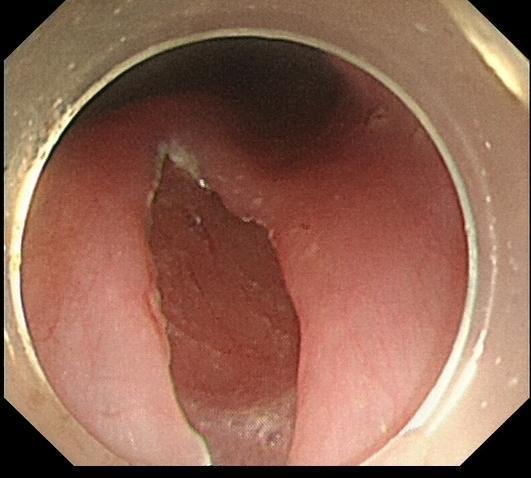

24岁男性患者,因“吞咽困难2年余”之主诉入院,2年前,患者出现吞咽困难症状,可进全流食,不能进固体食物;有饭后胸部胀痛,反流,呕吐症状,呕吐物为食物残渣;来我院内镜中心行胃镜检查示:食管下段扩张受限,可见食物潴留,中上段食管可见扩张。考虑贲门失迟缓。后患者行食管造影,表现为典型鸟嘴征,明确为贲门失弛缓症。遂来我院行POEM手术。

内镜检查示:食管下段扩张受限